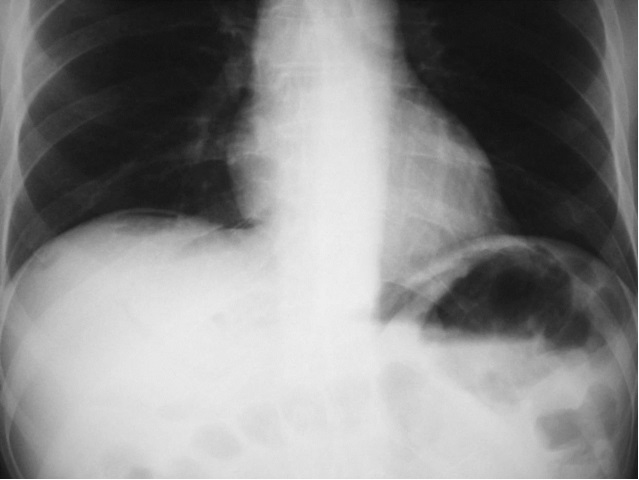

胆汁性腹膜炎

Transhepatic track embolisation Haemostasis (venous) Bile leak Embolisation Options Coils Glue Gelfoam 术后肩膀痛